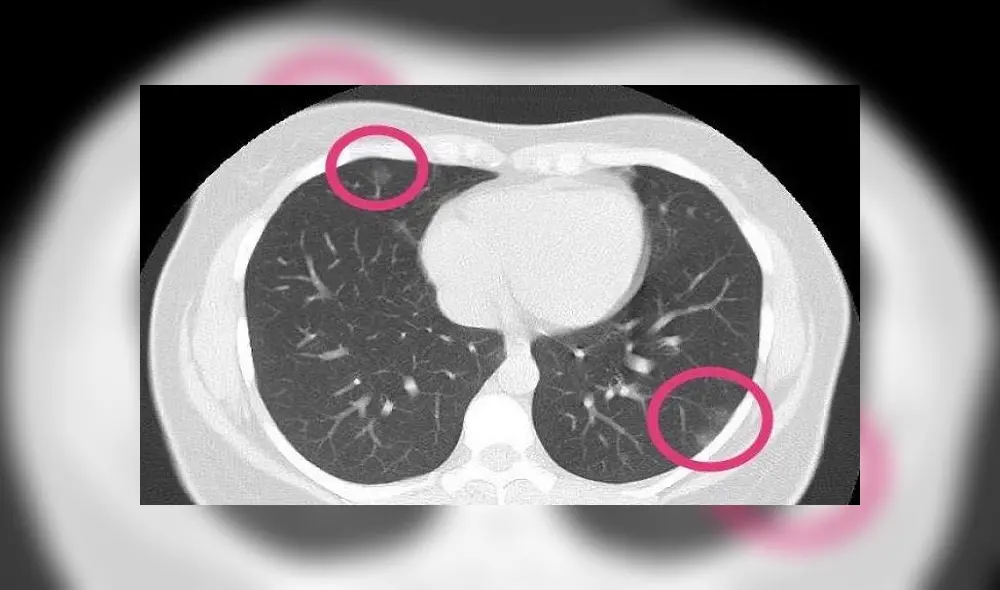

Las imágenes desvelaron zonas de opacidad en los pulmones, es decir, había líquido en ese órgano respiratorio.

El caso de una mujer con COVID-19 en Pakistán. Las flechas apuntan a signos de punción y los círculos indican evidencia de neumonía